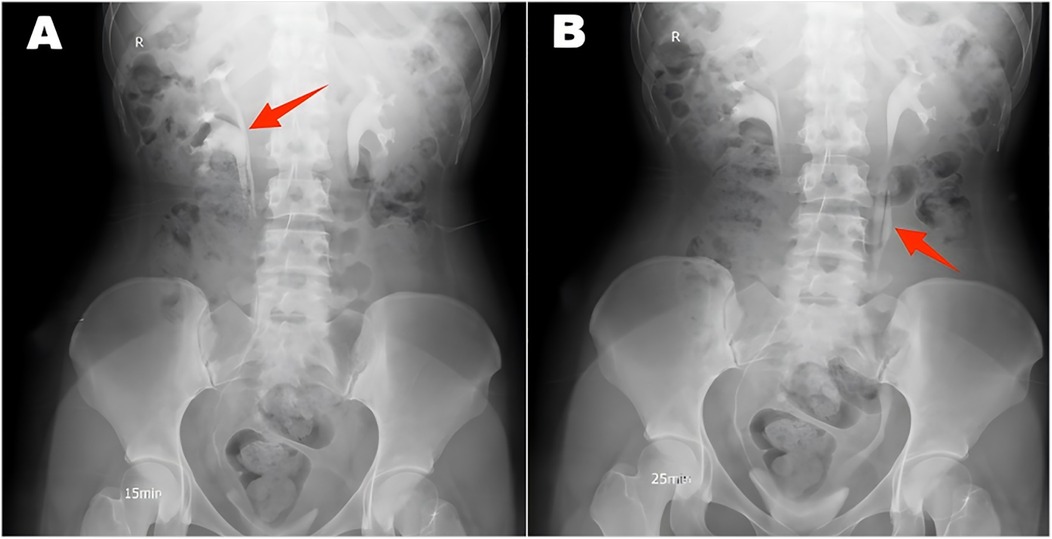

A 22-year-old female patient presented with persistent urinary incontinence since infancy, spanning over two decades. The patient's perineal area remains persistently moist, requiring 3–4 diaper changes daily. The patient had no significant past medical history and no familial history of similar conditions. No history of surgery or childbirth at the time of consultation. The patient grew up in an orphanage after being abandoned as an infant. Due to this socially vulnerable background and lack of longstanding familial support, her condition was neither brought to medical attention nor formally evaluated in childhood or adolescence. Clinical examination revealed thickening of the external urethral orifice, with a suspected vaginal opening measuring approximately 0.7 centimeters in diameter. To determine the cause of the patient's long-standing urinary incontinence, we conducted a series of systematic imaging and endoscopic investigations. Initial multi-slice CT imaging revealed compensatory enlargement of the left kidney with hydronephrosis affecting the entire renal pelvis and ureter. A cystic, low-density lesion connecting the distal ureter to the anterior vaginal wall was identified, suggesting a possible ectopic ureteral opening into the vagina (Figure 1). Magnetic resonance imaging of the urinary system confirmed bilateral renal abnormalities with double ureteral malformations, hydronephrosis on the left side, and ectopic opening of the left ureter into the anterior vaginal wall, accompanied by a bicornuate uterus. Intravenous urography (IVU) further confirmed bilateral ureteral anomalies on the right side, whilst the dilated left ureter exhibited a bifurcated pattern in its middle and upper segments, ultimately converging near the bladder, thus ruling out complete duplication (Figure 2). Cystoscopy revealed two openings in the right ureter consistent with a duplicated ureteral anomaly. An ectopic opening of the left ureter was identified near the external urethral orifice on the anterior vaginal wall. In contrast, the ureteral opening on the ipsilateral side of the bladder trigone was absent (Figure 3). It should be noted that a limitation in this case was the absence of renal scintigraphy to assess left renal segmental function. This examination is crucial for identifying such congenital anomalies, serving as a key basis for guiding clinical decision-making and selecting the surgical approach. The patient underwent transurethral cystoscopy and left ureter cystostomy under general anesthesia. Intraoperatively, the left ureteral orifice was found to be ectopically located on the anterior vaginal wall near the external urethral orifice. Additionally, approximately 2 cm above the external iliac artery, the ureter exhibited thickened adhesions spanning about 8 cm in length (Figure 4). The definitively identified ectopic opening location precisely matched the preoperative cystoscopy localization, confirming the diagnosis of congenital ureterovaginal fistula. Ureter cystostomy was performed by creating a subcutaneous tunnel, excising the redundant ureter segment, and anastomosing it to the bladder mucosa, with a double-J stent placed. Postoperative urinary incontinence symptoms were completely resolved, and the patient was discharged successfully on the fourth postoperative day. During the two-month follow-up period, the patient reported having completely discontinued the use of urinary pads. Ultrasound follow-up revealed complete resolution of left hydronephrosis with no significant ureteral dilatation observed. After two months postoperatively, the double-J stent was removed via cystoscopy, and the patient's urinary function returned to normal.

Figure 2. Intravenous urography revealed a double ureter on the right side (A) and a double ureter on the left side, which converged into a single ureter (B).